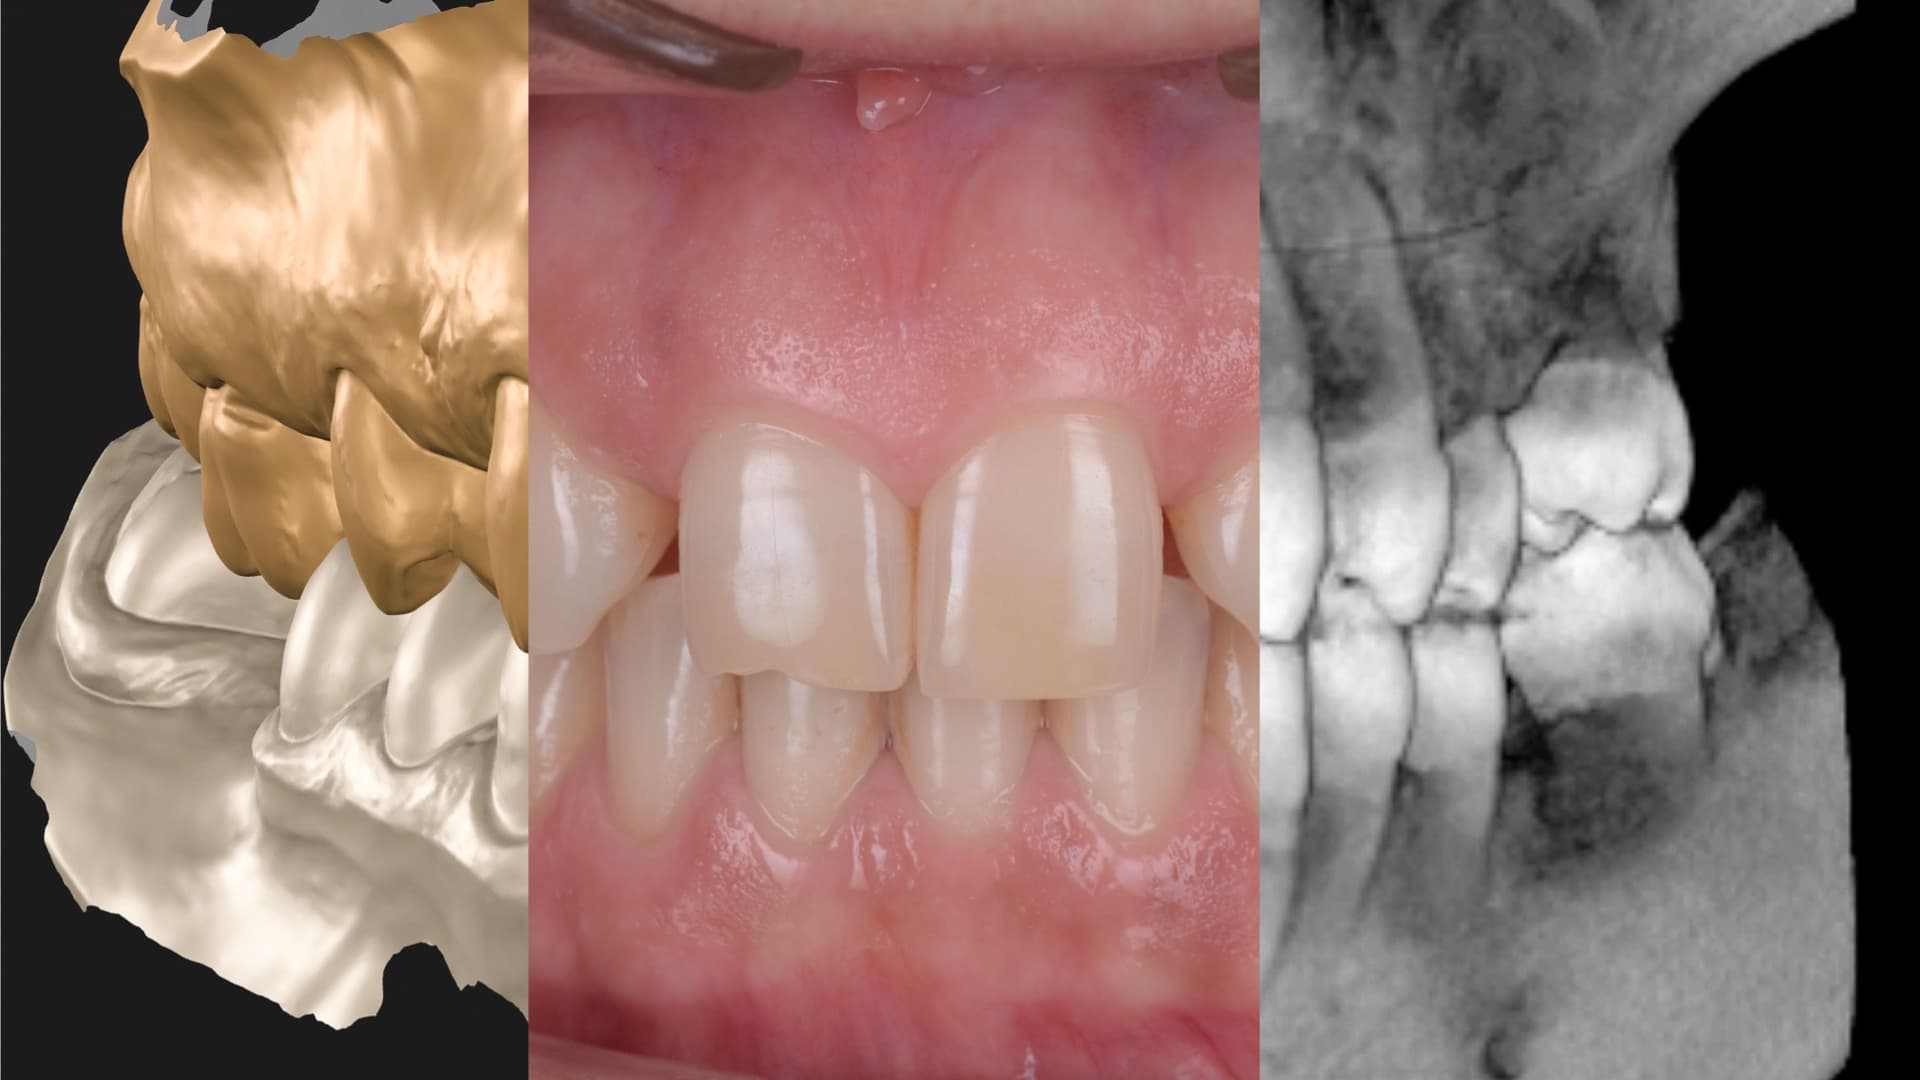

Fiecare caz cu alignere începe cu un plan digital ghidat facial. Folosind scanări 3D, analiza ocluziei și fotografii, simulăm rezultatul ideal înainte de a mișca vreun dinte. Astfel, fiecare etapă sprijină nu doar alinierea, ci și eventualele restaurări, nivelul gingival și stabilitatea mușcăturii.

După aprobarea planului, se realizează o serie de alignere personalizate care ghidează progresiv mișcarea dinților. Alignerele sunt detașabile, aproape invizibile și confortabile—ideale pentru pacienții care își doresc discreție. Fiecare aligner este bazat pe simularea aprobată, asigurând coerență între ceea ce s-a planificat și ceea ce se obține.